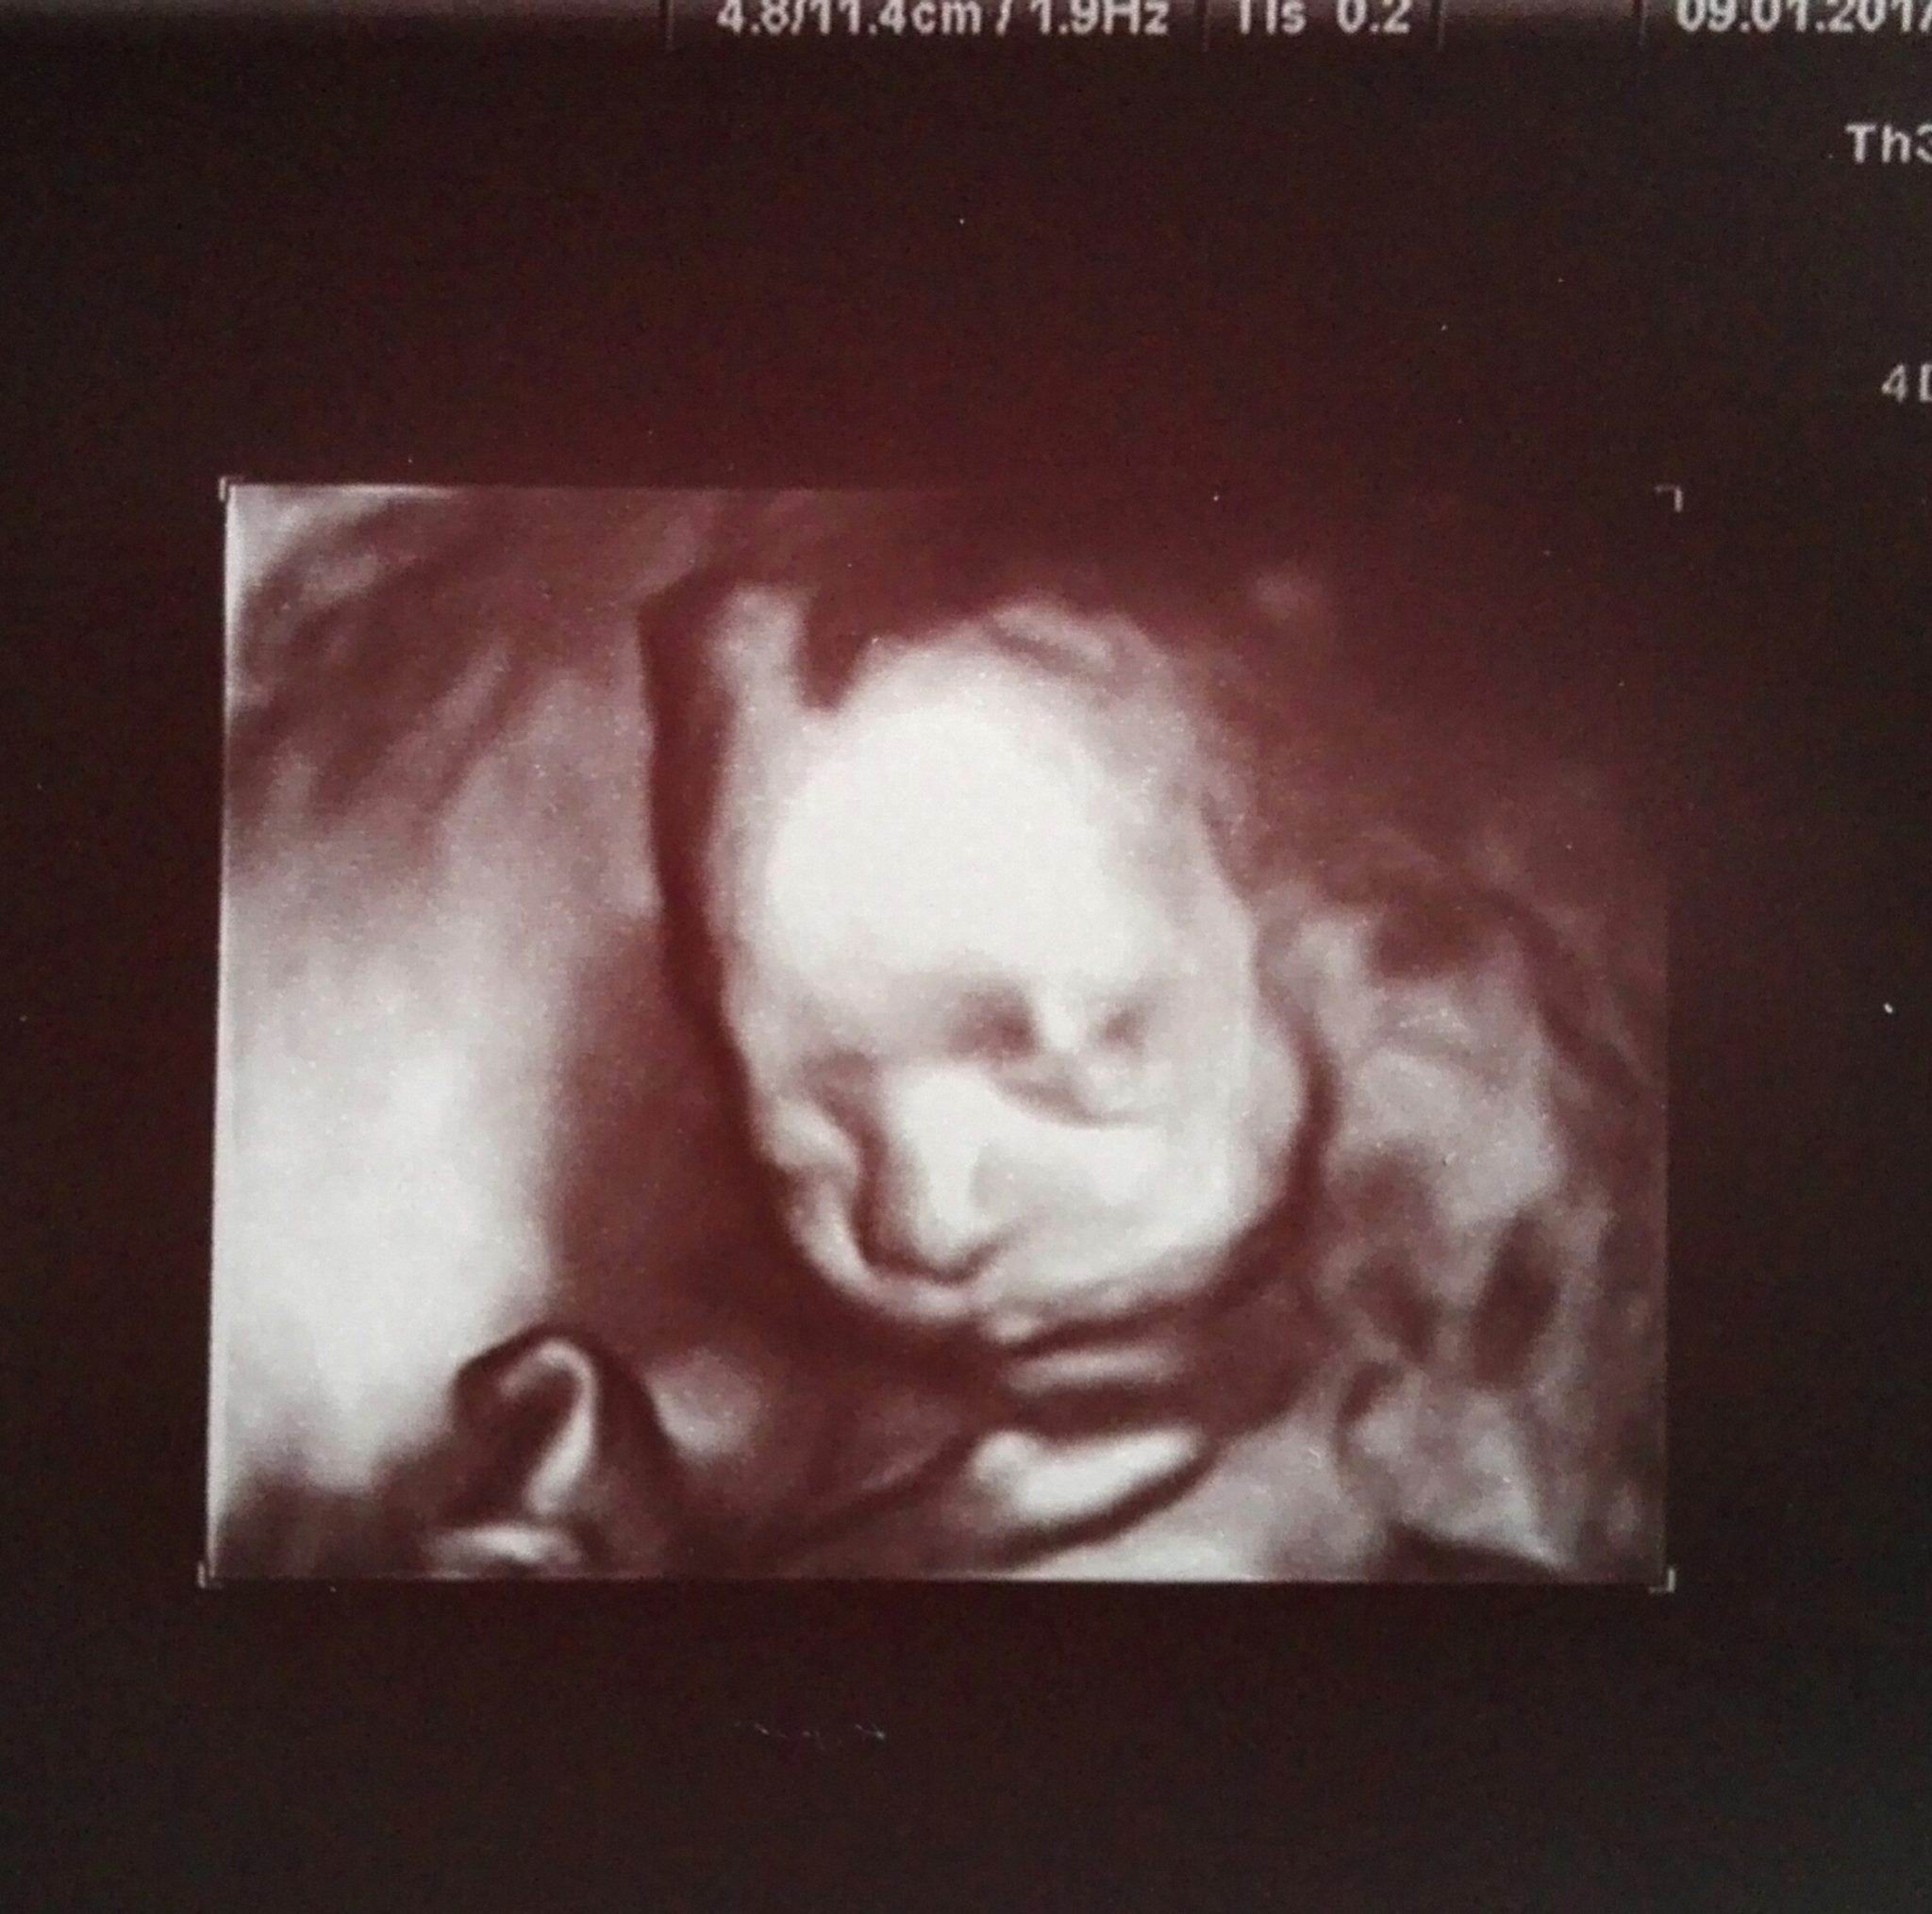

Dzień dobry, my dziś byliśmy na badaniu :)

Alicja waży 518 gramów, jest kompletna i proporcjonalna, narządy w środeczku działają jak należy, paluszki u rączek policzone, ułożona jeszcze głową do góry ale macica już wysoko ponad pępkiem, stąd kopniaki pod żeberko, termin ustalony na 4 maja - CC, następna wizyta 6 lutego i mam zrobić krzywą cukrową, mocz i morfologię. moje 10 kg in plus ocenione na "w porządku", ciśnienie 130/70, zwolnienie i siedzenie w domu :)

• Ala 22 t5d.jpg

Ala 22 t5d.jpg